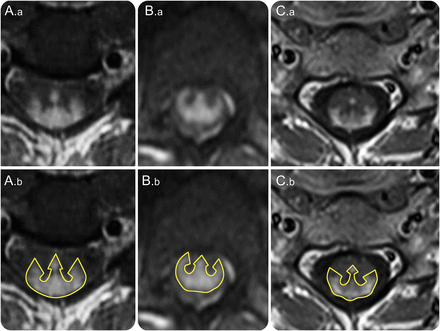

新月形的分层后单纯的增强伴随着中央管增强导致一个三管齐下的外观(。a、B。a, C。a) resembling a trident head (A.b, B.b, C.b).